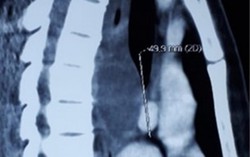

Nuốt nghẹn, khó thở đi khám phát hiện kén phế quản có thể gây xẹp phổi

Khoảng 3 tháng trước, bệnh nhân có biểu hiện nuốt nghẹn, không sốt, không ho. Gần đây, bệnh nhân khó thở nhẹ khi vận động nên đã đi khám và được kết luận bị kén phế quản.